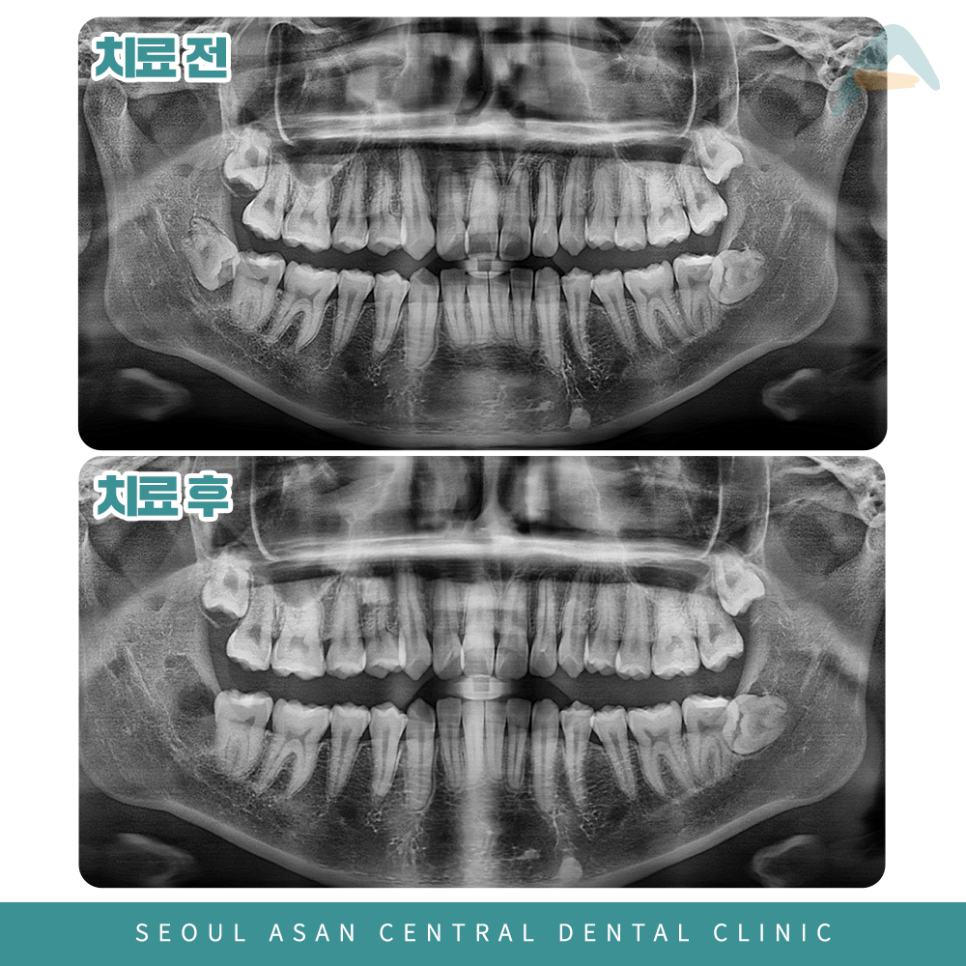

엑스레이 사진을 통해서 발견이 가능하기 때문에

양지동치과에서는 발치 전에 CT 촬영을 진행하여

사랑니의 기울기 형태와 물혹의 크기,

인접 치아 상태, 신경 등등을 꼼꼼하게 확인 후

치료를 결정하게 됩니다.